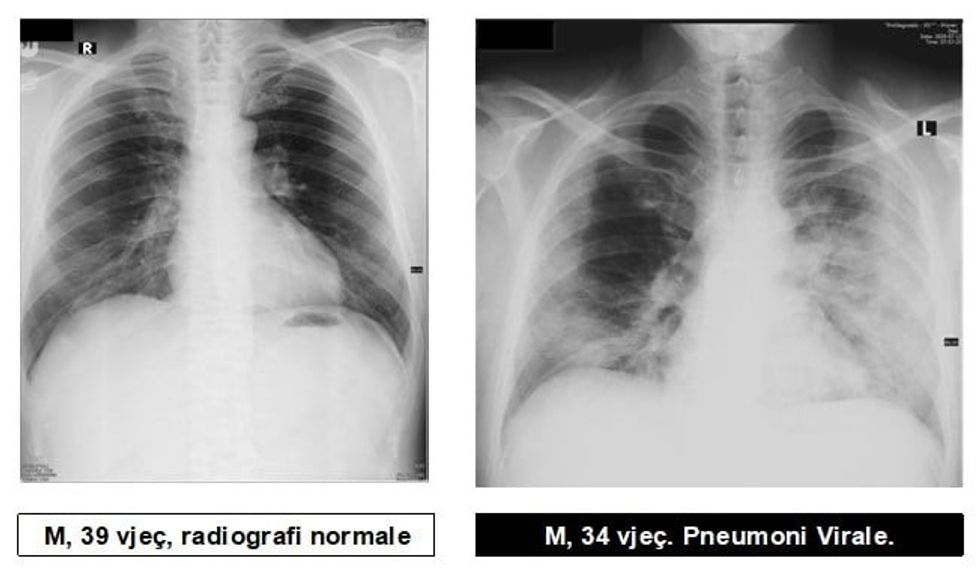

Radiologu në Spitalin Rajonal të Prizrenit, Sylejman Krasniqi tregon pamjet e mushkërive të pacientëve me pneumoni virale.

“Për te gjithë ata që maskat i kane veç si dekorim, për ata që distancën sociale e kanë diçka të huaj dhe për të gjithë ata që nuk i respektojnë këshillat e institucioneve relevante Shëndetësore, këto imazhe le të ju shërbejnë që ta kuptoni se megjithatë virus ka, pandemi ka dhe situata nuk është e mirë”, ka shkruar Krasniqi, përcjell Telegrafi.